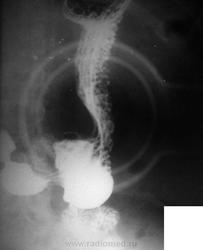

Блюдцеобразный рак желудка? (Аденокарцинома низкой степени дифференцировки)

Мужчина 1953 года рождения, лежит в кардиологии, проходил год назад ФЭГДС выявлена язва по малой кривизне, по биопсии гастрит. Сейчас при УЗИ органов брюшной полости утолщение стенки желудка, кокарда. Направлен на рентгенолргическое исследование желудка, вот результат...

Аденокарцинома низкой степени дифференцировки.

После того как эндоскопист в пятницу увидел снимки, он не мог ждать до среды, сегодня проведено ФЭГДС: Заключение эндоскописта (на словах): рак желудка, распад, скорее всего пенетрация. Результаты биопсии через 10 дней возможно пораньше.

Эндоскопически тянет на хроническую пенетрирующую язву, осложненную кровотечением, тип Forrest Ib. Повезло Вам с эндоскопистом, если он не "усидел" при виде снимков - значит, рутина не забила творческого интереса к медицине!

Добавлены результаты биопсии: